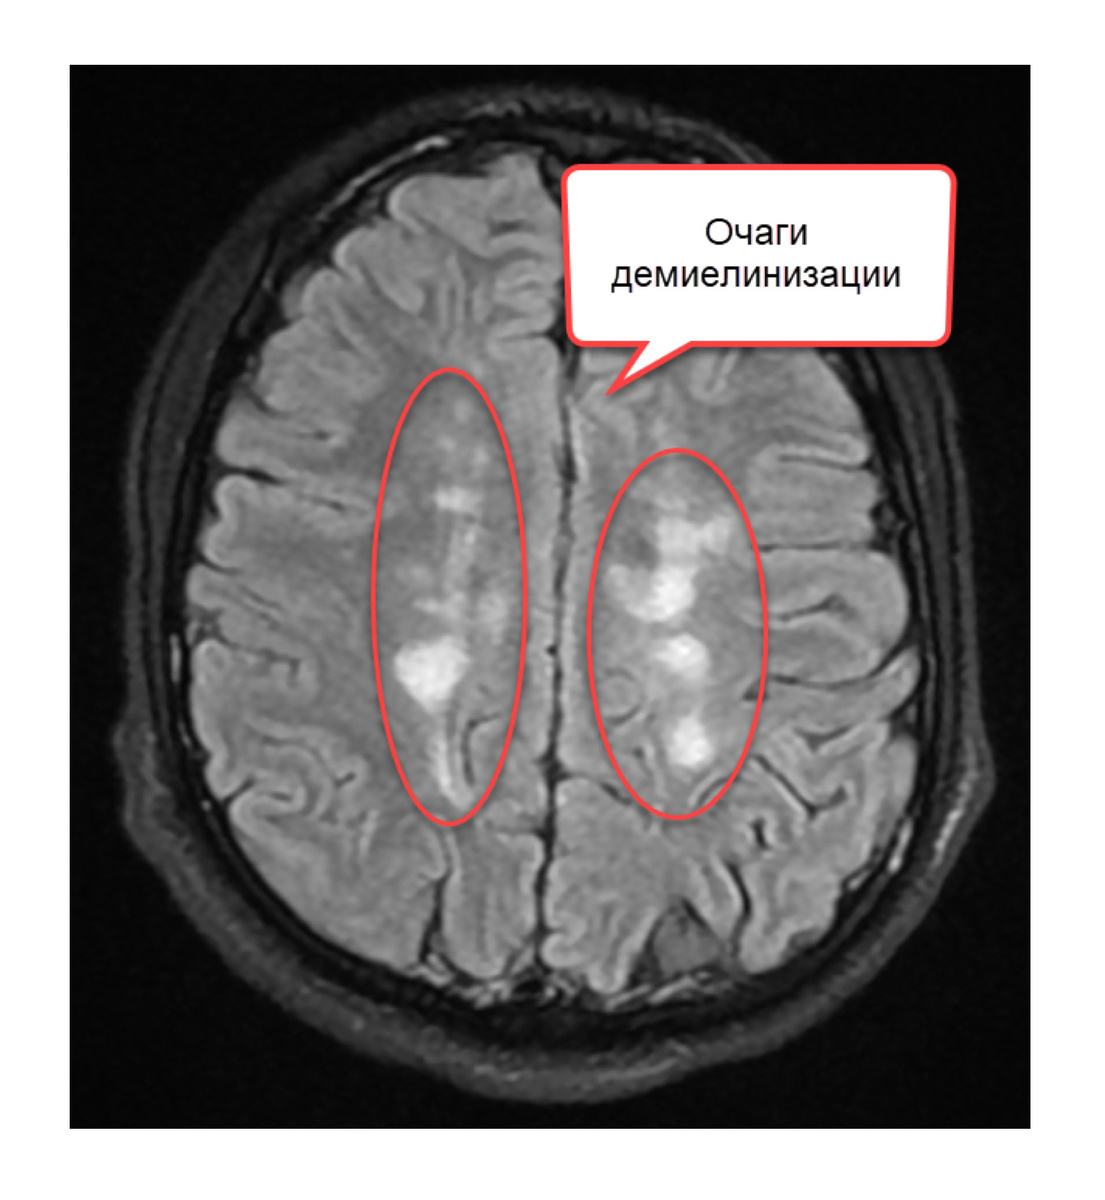

Очаги в головном мозге при рассеянном склерозе называют демиелинизирующими бляшками. Собственно, термин склероз (σκληρία) переводится с древнегреческого как «твёрдость, плотность, затвердение, уплотнение». Таким образом, демиелинизирующая бляшка – это зона уплотнения с разрушенным миелином. Но, как оказалось, не все бляшки одинаковые. В 10-х годах этого века проведено большое исследование, включающее анализ головного мозга людей, страдающих рассеянным склерозом. В результате исследований были выделены 4 типа бляшек: 1️. Активная бляшка, в которой происходил распад миелина, было много воспалительных клеток. Активные были подразделены в свою очередь на ранние и поздние. 2️. Неактивная – имеет чёткую границу, нет клеток воспаления. На МРТ не накапливает контраст. 3️. Бляшка-тень – это бляшка, но с полностью восстановившимся миелином. Это те самые бляшки, которые на фоне терапии могут «пропасть» на последующих МРТ. 4️. Тлеющая бляшка – это медленно растущая бляшка с валом из акт

Очаги в головном мозге при рассеянном склерозе называют демиелинизирующими бляшками. Собственно, термин склероз (σκληρία) переводится с древнегреческого как «твёрдость, плотность, затвердение, уплотнение».

Таким образом, демиелинизирующая бляшка – это зона уплотнения с разрушенным миелином. Но, как оказалось, не все бляшки одинаковые. В 10-х годах этого века проведено большое исследование, включающее анализ головного мозга людей, страдающих рассеянным склерозом.